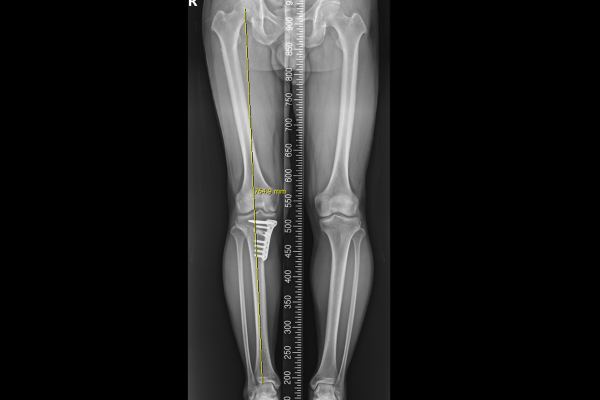

이후 스페이서(Spacer)를 삽입하여 다리 각도 교정과 함께 공간을 확보하고, 금속판으로 고정하며 수술을 마칩니다.

수술은 성공적으로 마치게 되었고, 수술 후 X-RAY를 보면, 기존에 안쪽에 있던 체중선이 중간에서 살짝 바깥쪽으로 잘 이전되었고, 다리축이 일자로 교정되었음이 확인됩니다.